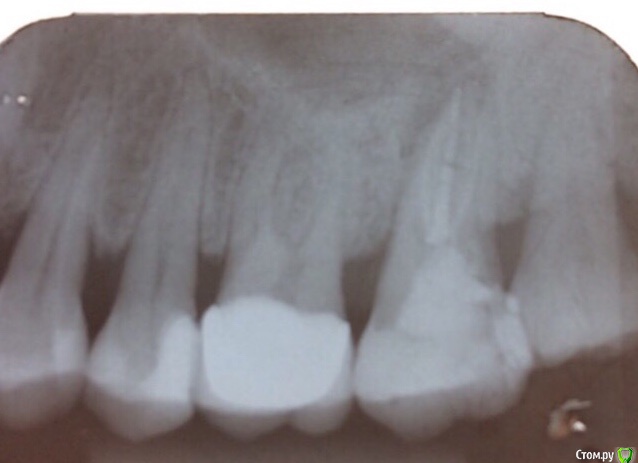

Oxi78 Опубликовано 7 сентября, 2019 Поделиться Опубликовано 7 сентября, 2019 Добрый день. Имею проблему с 27 зубом. Пошла к стоматологу. Сделали снимок. По снимку инфекция в районе корня. Сказали можно или удалить зуб или попробовать пить антибиотики и потом лечить зуб обязательно с применением микроскопа. Уважаемые стоматологи посмотрите пожалуйста снимок. Можно ли спасти этот зуб. Можно ли по этому снимку оценить состояние кости вокруг других зубов. Спасибо. Ссылка на комментарий

krokomot Опубликовано 7 сентября, 2019 Поделиться Опубликовано 7 сентября, 2019 Шансы есть. 2 Ссылка на комментарий

Гарриевич Опубликовано 16 сентября, 2019 Поделиться Опубликовано 16 сентября, 2019 лечить можно, микроскоп опционно Ссылка на комментарий